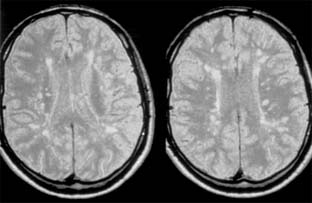

During an acute episode of optic neuritis, MRI shows gadolinium enhancement, increased signal on short tau inversion recovery (STIR) sequences, and sometimes swelling of the affected nerve. Brain MRI will show lesions consistent with demyelination in as many as 25% of patients with isolated optic neuritis (Figure 14-10). This does not establish a diagnosis of multiple sclerosis, though it does indicate a significantly increased risk of subsequent development of clinically definite multiple sclerosis. The value of steroid treatment in delaying the development of multiple sclerosis is greater in patients with abnormal brain MRI at presentation. Thus, brain MRI may be indicated in isolated optic neuritis if more precise information is wanted about the risk of multiple sclerosis and the value of systemic steroid treatment.

Figure 14-10

Figure 14-10: Cerebral hemisphere white matter lesions on MRI associated with acute demyelinative optic neuritis.